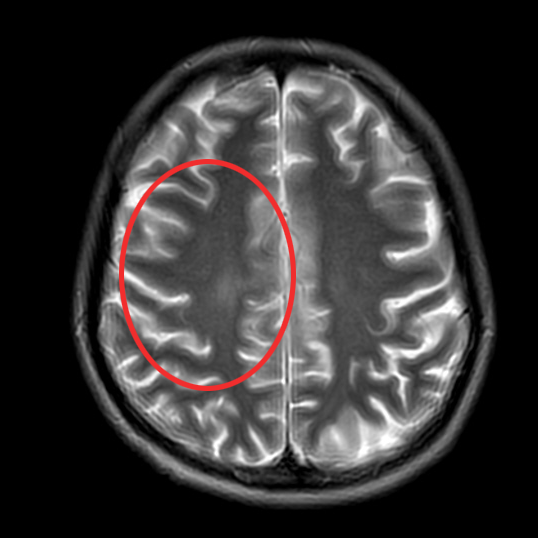

▲治疗后1月

▲治疗后2年半

随访至今

肺部、颅内、可见淋巴结、腹腔等

多处病灶完全缓解

患者日常生活无异于常人